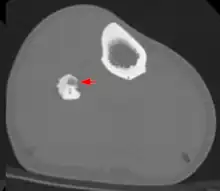

Radiographs in osteoid osteoma typically show a round lucency, containing a dense sclerotic central nidus (the characteristic lesion in this kind of tumor) surrounded by sclerotic bone. The nidus is seldom larger than 1.5 cm.

The lesion can in most cases be detected on CT scan, bone scans and angiograms. Plain radiographs are not always diagnostic. MRI adds little to the CT findings which are useful for localisation. Radionuclide scanning shows intense uptake which is useful for localisation at surgery using a hand held detector, and for confirmation that the entire lesion has been removed.[8][9]